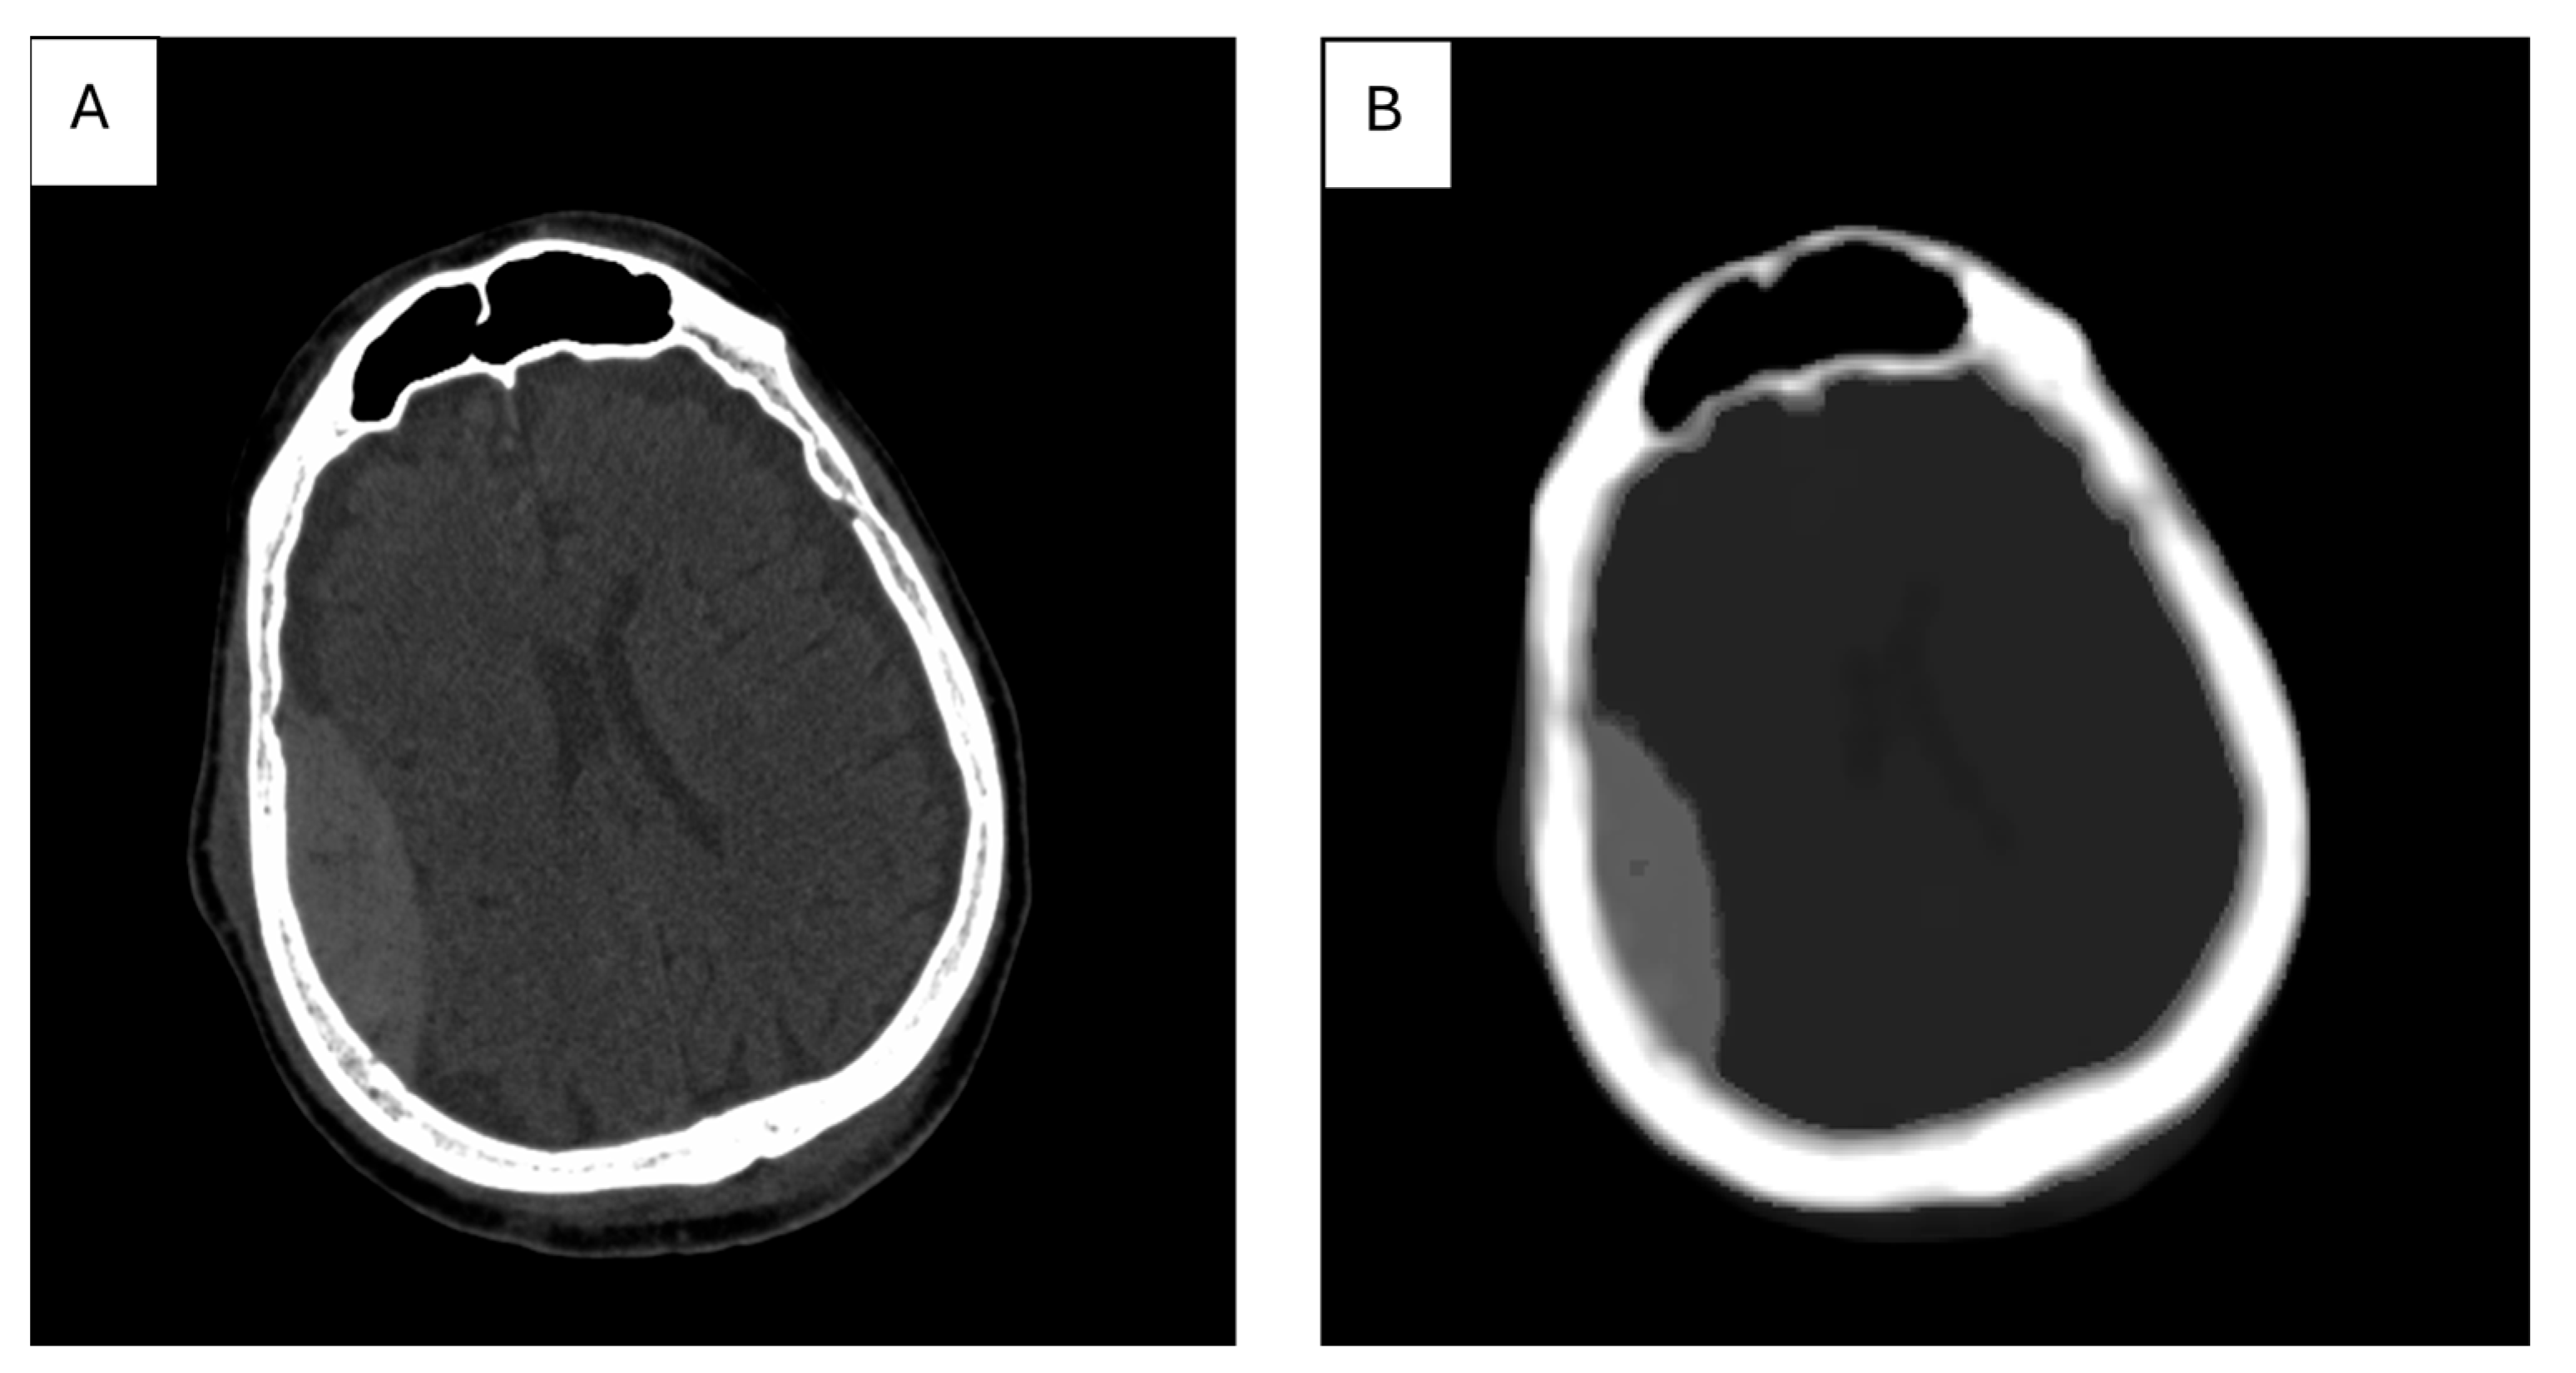

7. The Role of Textural Analysis in Image Preprocessing